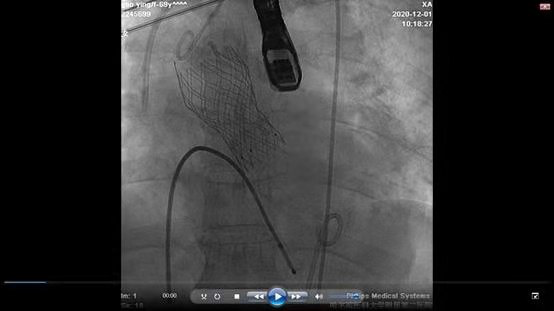

主动脉人工瓣成功植入

ac米兰官网中文网站二院心内科TAVR团队进行了评估,认为张大爷符合TAVR手术指征。 经过与家属的充分沟通后,手术如期举行。ac米兰官网中文网站二院心内科TAVR团队张东会医生、杨光医生、陈涛医生,三人通力协作,在超声医学科、麻醉科等学科配合下,独立完成了穿刺双侧股动脉入路,并将经导管成功置入人工主动脉瓣。手术历经2小时,顺利结束,张大爷心功能明显改善,无任何不适症状。术后第二天复查心脏彩超心脏收缩功能完全恢复正常,张大爷可以下地自由活动。